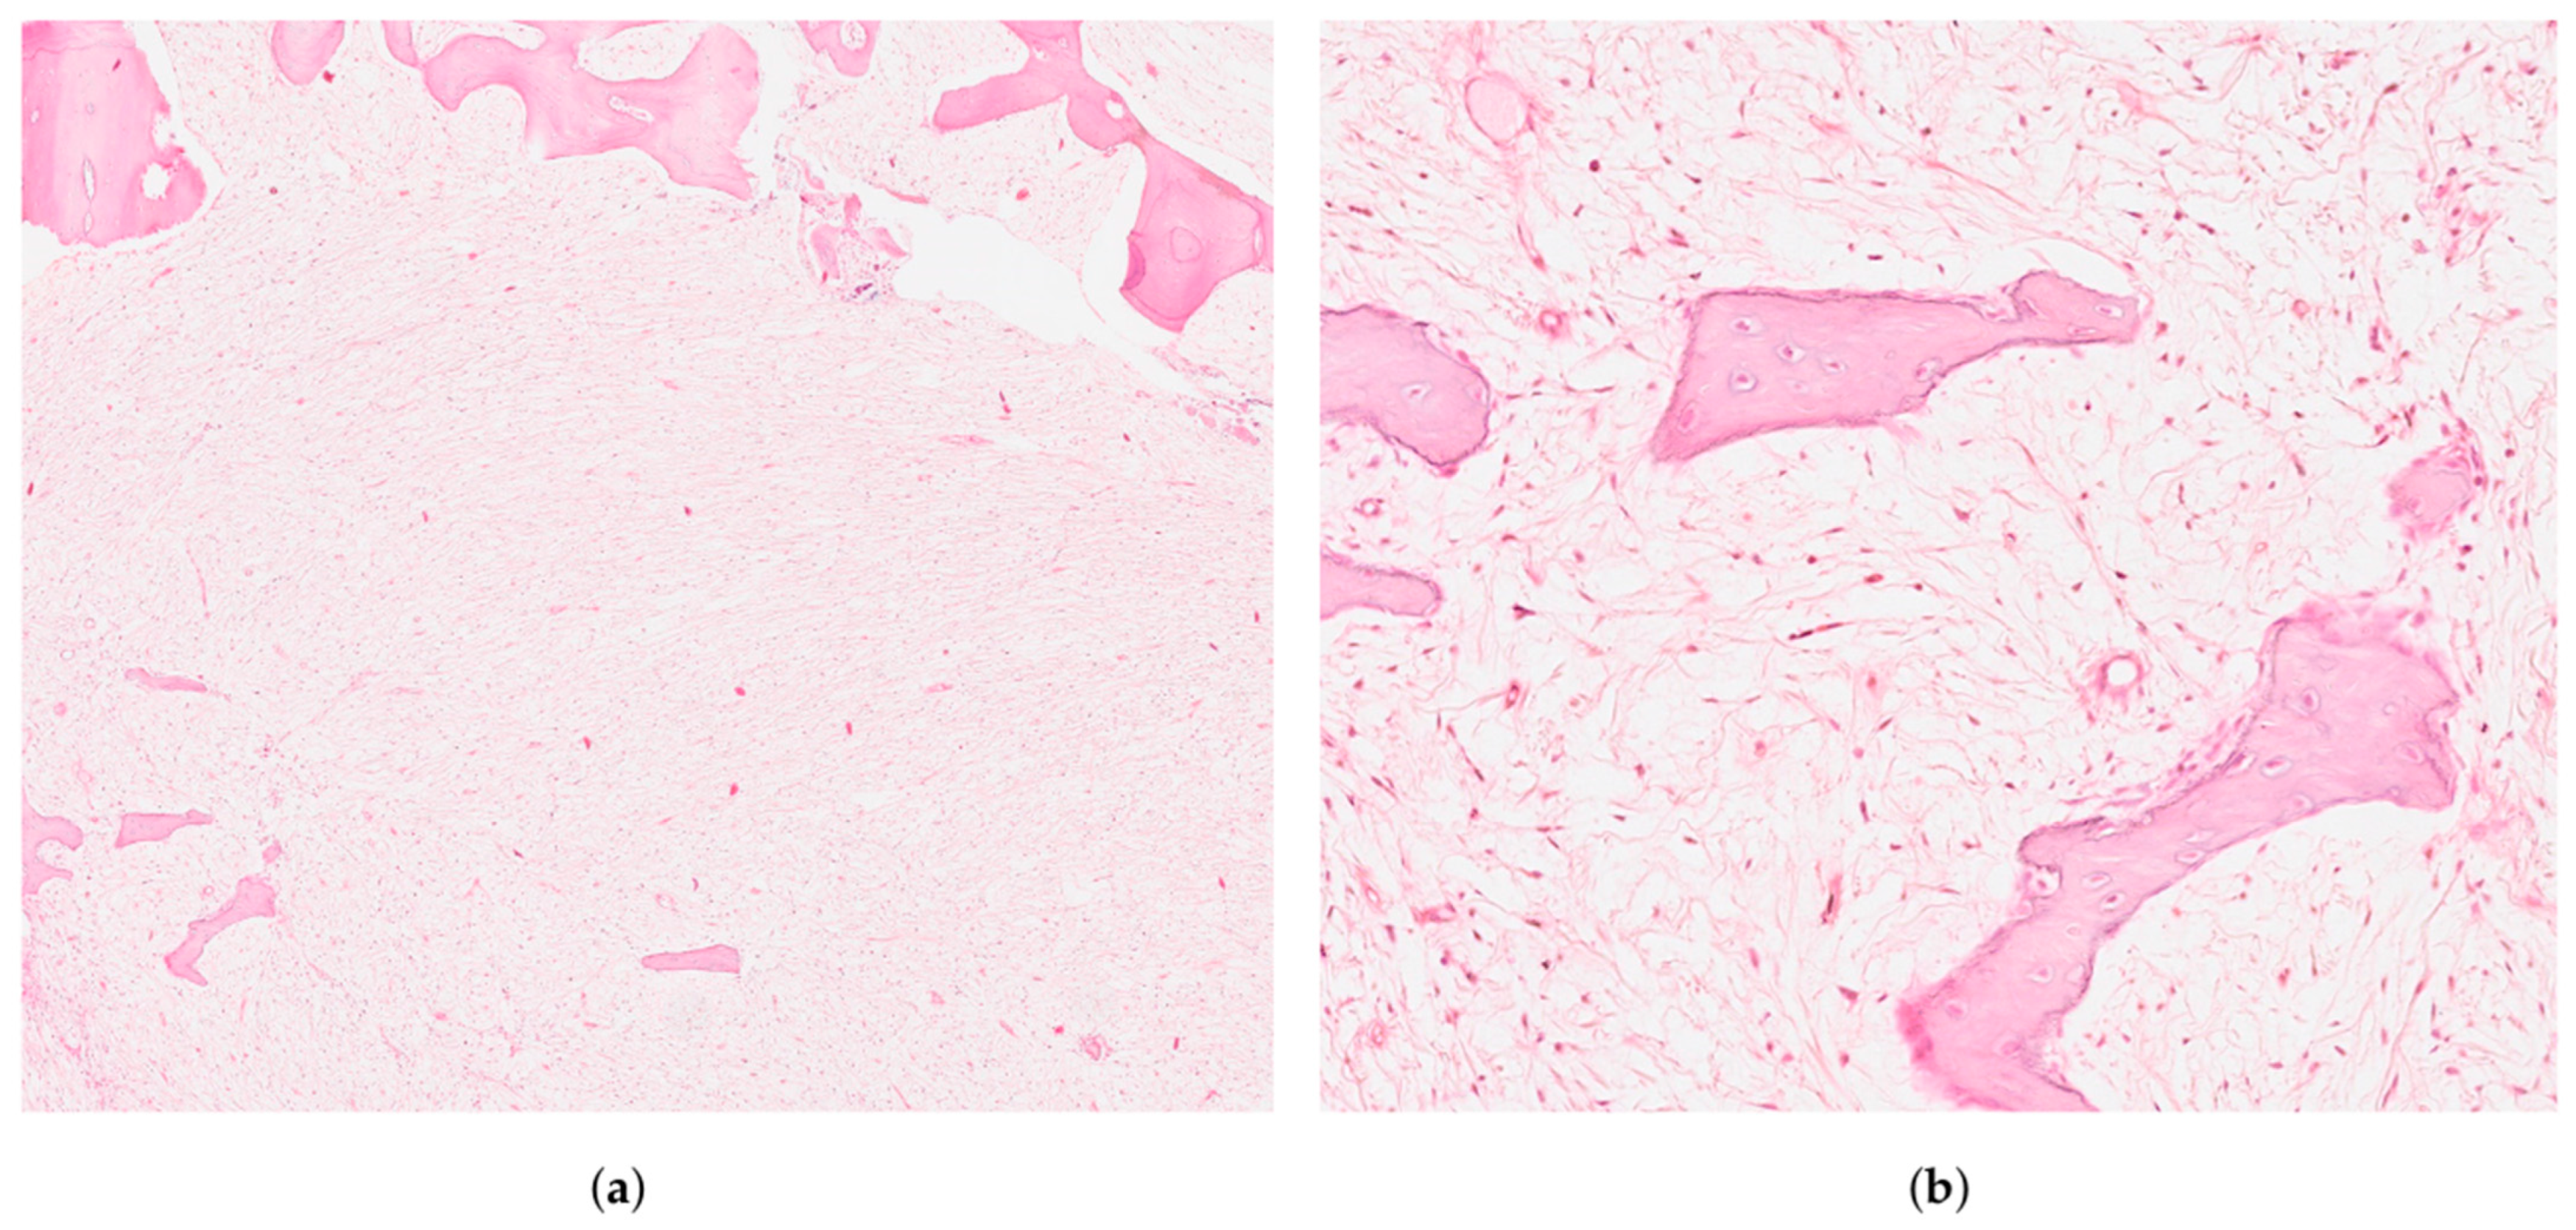

2.2. Treatment Procedures and Histopathological Results

| Histology and Odontogenic Epithelium | Spindle and stellate-shaped cells in a myxoid stroma with prominent collagen fibres. Possible remnants of odontogenic epithelium, aiding differentiation from odontogenic myxoma | [4,13,14] |

| Histopathology | Spindle and stellate cells in myxoid stroma with collagen fibres | Islands of odontogenic epithelium resembling enamel organ | Lobules of chondroid and myxoid tissue with spindle cells | Spindle-shaped cells in myxoid matrix, mild atypia | Malignant osteoid production by atypical osteoblasts |